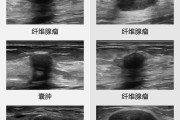

破局“她健康”,迈瑞医疗领跑数智影像新赛道详细阅读

近日,迈瑞乳腺超声辅助评估软件通过国家药品监督管理局评审,正式进入创新医疗器械特别审查程序。 基于人工智能技术,该产品是国内乳腺超声领域首个进入三类创新医疗器械特别审查程序的AI辅助诊断产品。通过规范...